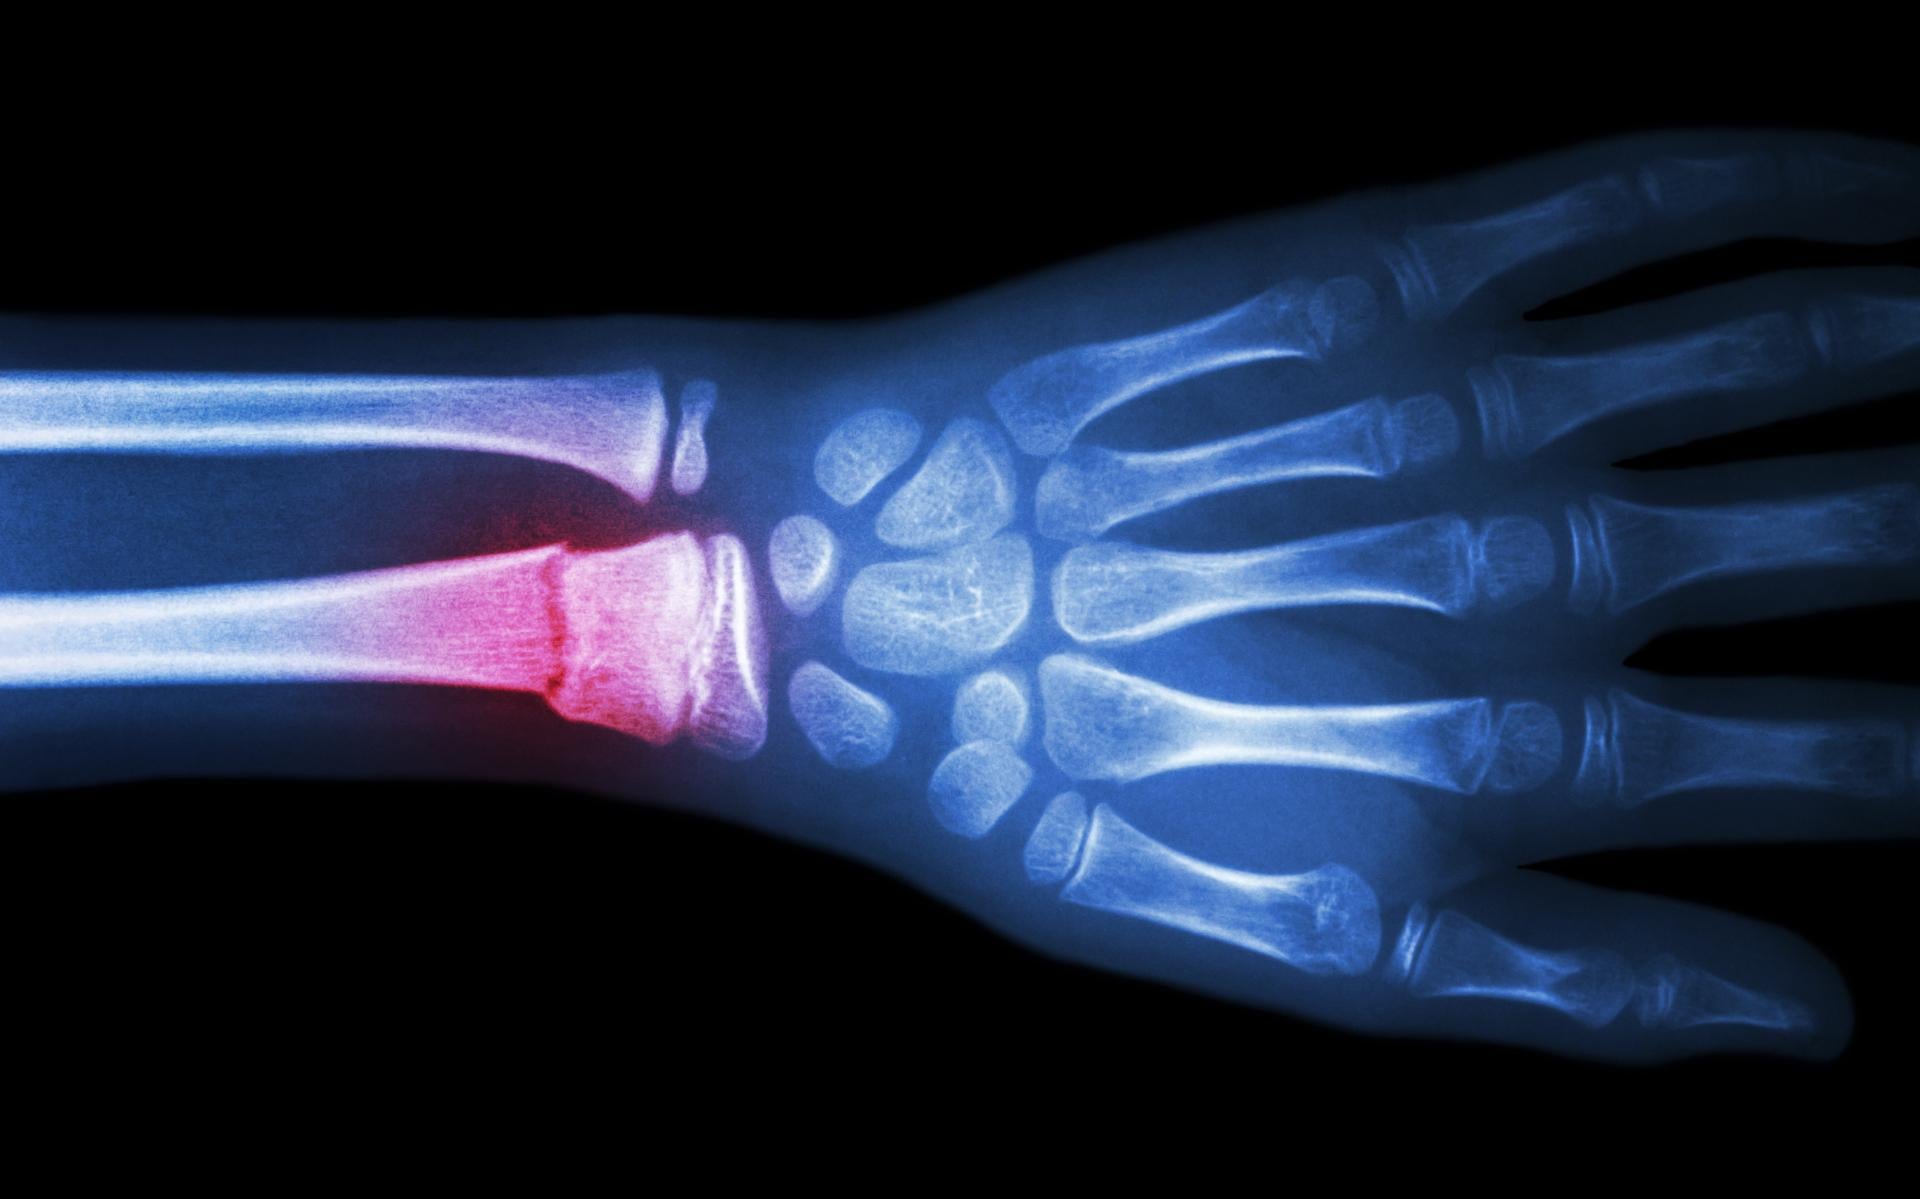

高血壓是十分常見的長期病,但原來血壓過高不只影響心血管健康,更可能增加骨質疏鬆的風險。最近一項小鼠研究發現,高血壓可加速年幼動物流失骨質的速度,情況就如年老衰退一樣,因此控制血壓可能是骨骼健康的關鍵環節。

結果發現,注射荷爾蒙藥物後患上高血壓的年輕小鼠,骨質水平、骨骼結構及強度都明顯轉差,程度與年老小鼠的正常骨骼退化相若,反映高血壓可能是骨質疏鬆症的成因之一。進一步分析更發現,用藥引起高血壓的年輕小鼠,與年老小鼠一樣,骨髓中含有更多免疫細胞,但健康小鼠身上則沒有這情況,故此推斷這種炎症反應正正是高血壓影響骨質的原因。

今次研究則反映年紀輕輕便患高血壓,骨質可能更早流失,導致骨折風險上升。